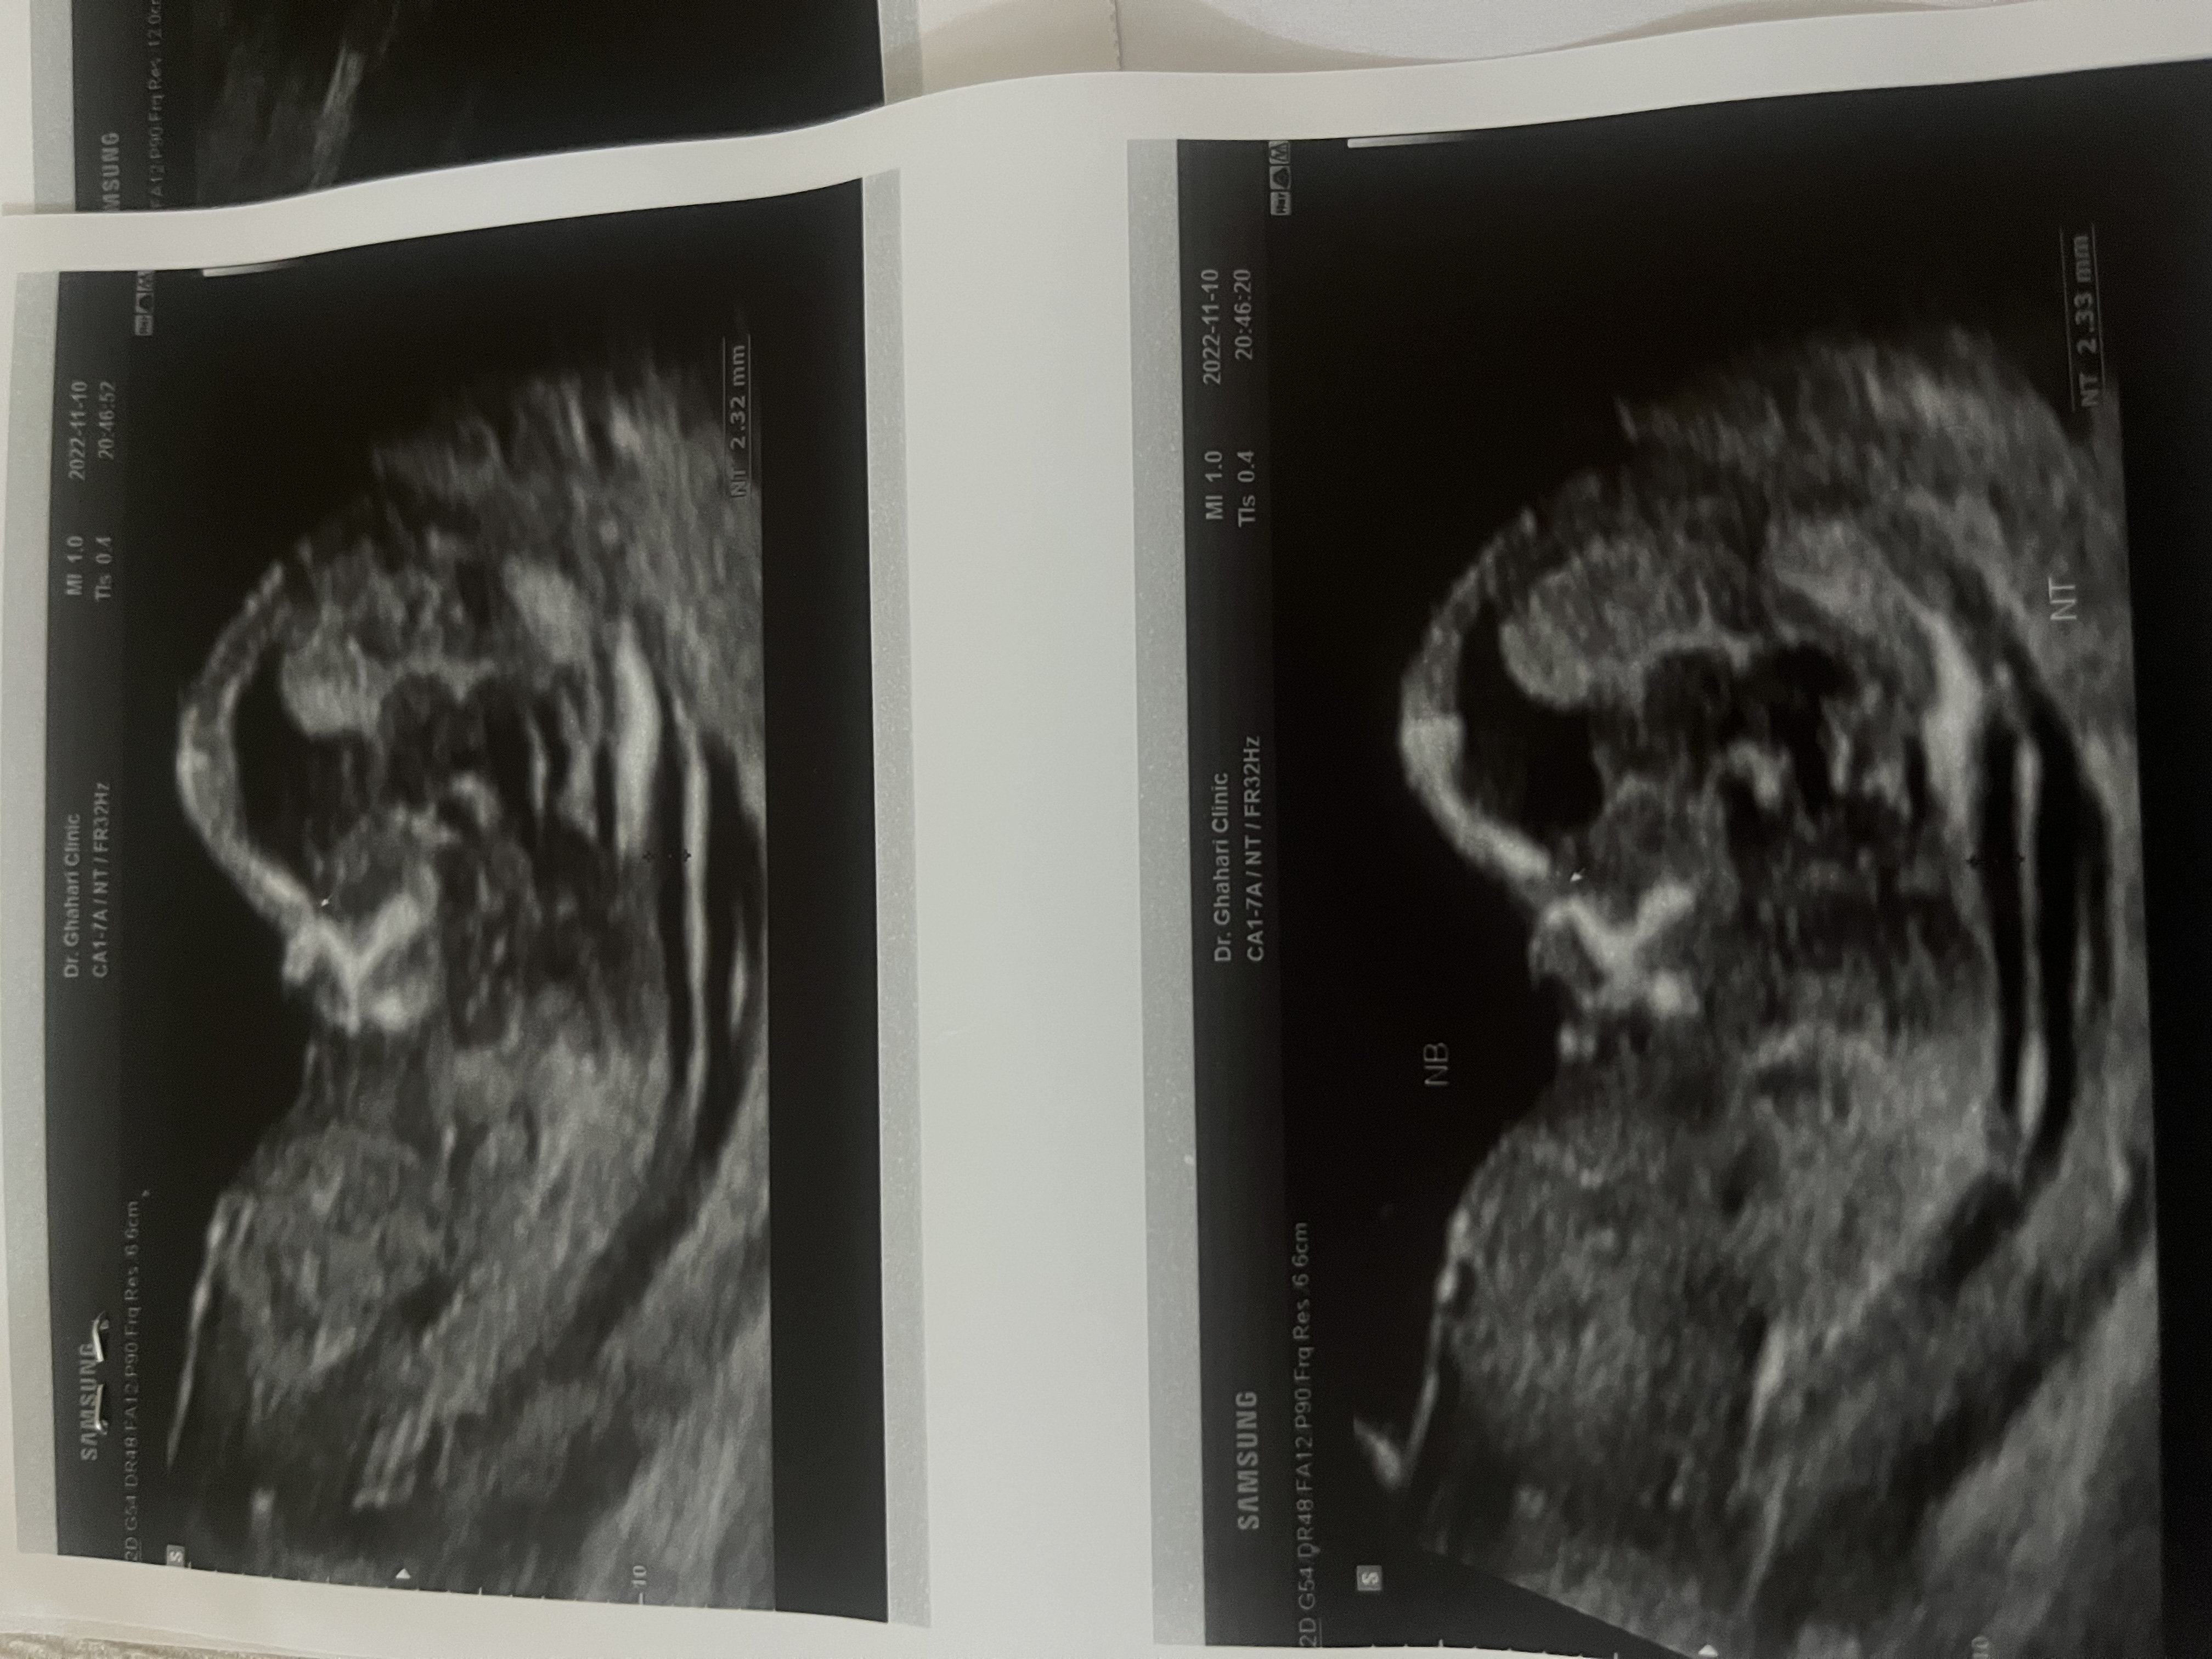

بنظرتون جنسيت چيه ؟؟

الان عكس سونگرافي ميزارم

چن هفته ای؟

نزديك ١٤

ان تي بهم گفت پسره

يني اشتباه گفته؟؟